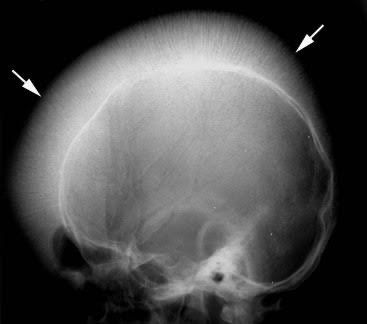

Hair on end sign on X-ray skull is a typical finding seen in cases of chronic hemolysis. This sign is usually seen in cases of blood disorders like thalassaemia and sickle cell anemia. This condition results from the hyperplasia of bone marrow to compensate for the RBCs lost during the process of excessive hemolysis. Picture credit: https://radiologykey.com/bone-marrow-disorders/